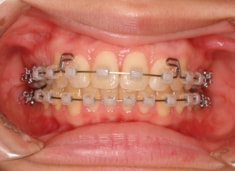

治療前

治療開始時